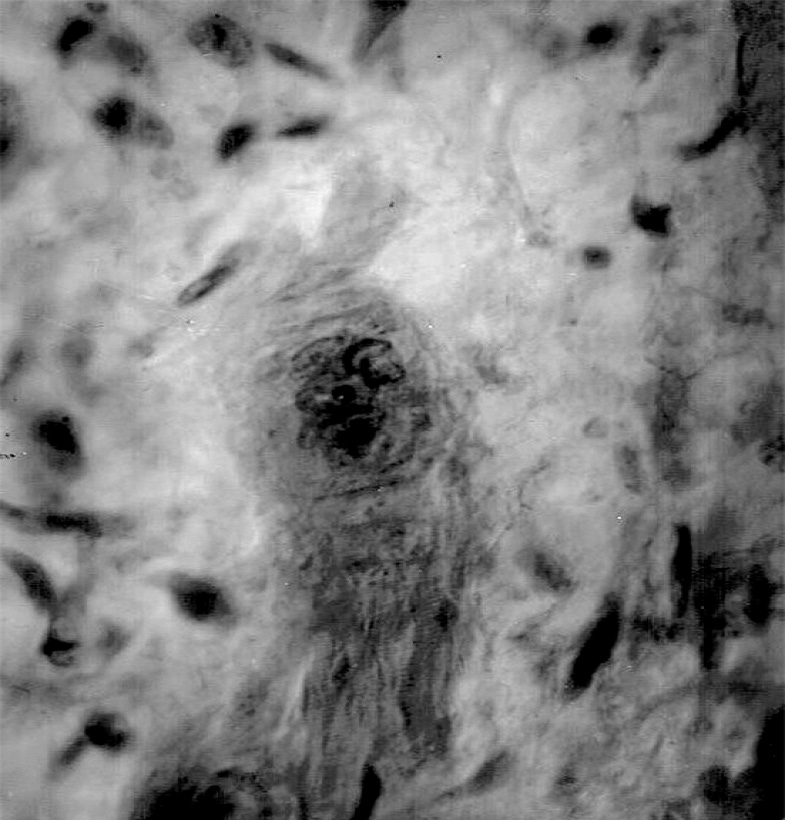

Наряду с пролиферацией кардиомиоцитов на 2–4-е сутки после травмы в очаге повреждения и на границе с ним в сохранившейся ткани определялись низкодифференцированные структуры мышечного типа. В одних случаях это были концевые отделы повреждённых кардиомиоцитов на границе с участком повреждения, вдающиеся в участок травмы на некоторое расстояние. При этом они приобретали булавовидную форму, цитоплазма их окрашивалась эозином слабо и была полностью лишена исчерченности; концевые отделы этих образований содержали большое число ядер (рис. 1). В других случаях низкодифференцированные структуры представляли собой крупные клетки веретенообразной формы, лежащие в очаге повреждения. От фибробластов эти клетки отличались окраской цитоплазмы эозином и равномерно распределённым по крупному ядру нежным хроматином (в отличие от глыбчатого расположения хроматина в ядрах фибробластов). Эти образования очагово объединялись в группы, формируя цепочки (рис. 2).

Рис. 1. Сердце плода кролика на 3-и сутки после операции: дедифференцированный концевой отдел повреждённого кардиомиоцита на границе с очагом травмы. Окраска гематоксилином и эозином, ×900.

Fig. 1. The heart of a rabbit fetus on the 3rd day after surgery: the dedifferentiated terminal section of the damaged cardiomyocyte is on the border with the focus of injury. Stained with hematoxylin and eosin, ×900.